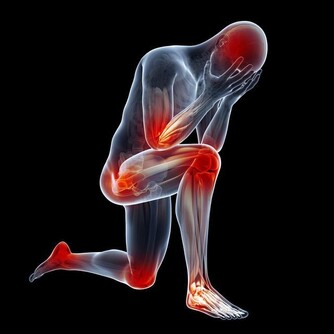

但問題是,在運動後和高溫條件下,特別是長時間、高強度運動,會大量消耗體內的鎂

,從而讓血清中的鎂明顯下降,降低肌肉的活動功能,甚至還會發生抽搐、痙等。

這表明,我們體內已經嚴重缺乏鎂了。